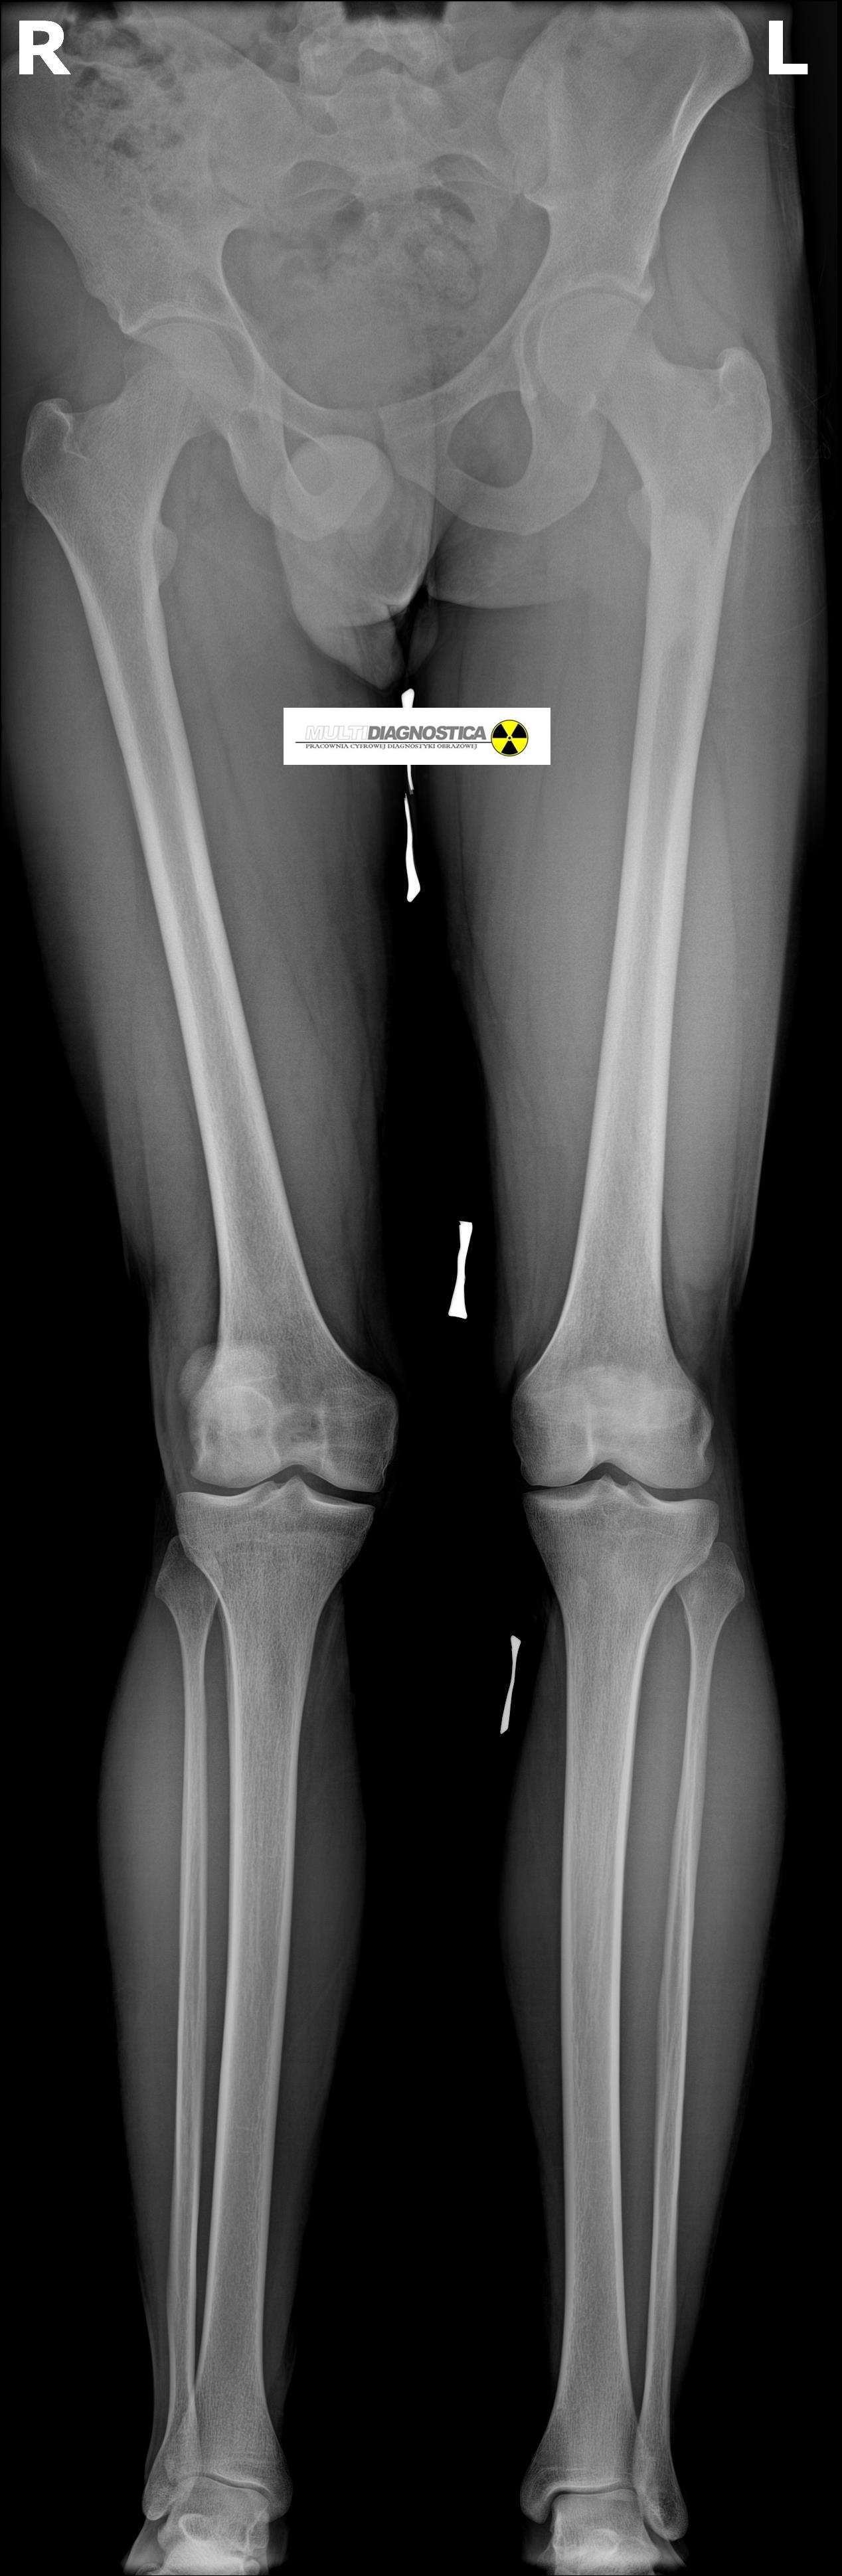

Wyposażyliśmy pracownię w cyfrowy detektor z oprogramowaniem posiadającym funkcję skalometrii (Stitching), dzieki której możliwe jest wykonanie badania telemetrycznego RTG całych kończyn długich i całego kręgosłupa a następnie uzyskanie obrazu diagnostycznego obejmującego razem kilka części anatomicznych połączonych w całość.

Skalometrie stosuje się w diagnostyce schorzeń ortopedycznych

Pomiary długości kości kończyn, kątowe pomiary skrzywień kręgosłupa